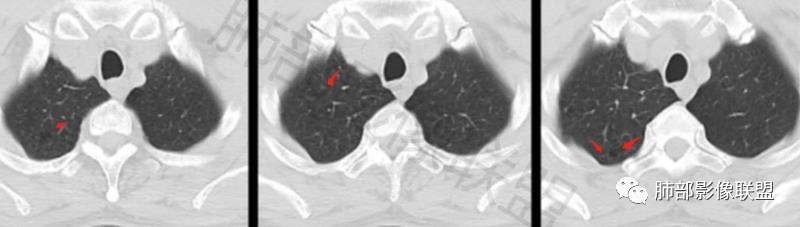

老年男性,左肺下叶背段胸膜下孤立结节,整体圆顿,周围有晕,晕中毛刺,似乎支持隐球,但边缘有一囊腔,恶性不能除外!等答案!

真有一囊腔在结节边缘

图做的真漂亮!老年男性,双肺多发结节,最大者位于左肺下叶胸膜下,周围有晕,晕中毛刺,边缘有一囊腔,胸膜牵拉,持续强化,考虑隐球,鉴别腺癌。

左肺下叶胸膜下类圆形结节,边缘光滑,周围有晕,晕中有毛刺,周围可见小卫星灶,相邻胸膜增厚,血管进入,右肺中叶可见小结节影,考虑炎性肉芽肿,隐球菌。鉴别腺癌。

老年男性,左肺下叶背段胸膜下结节,边缘毛刺,血管进入,斜裂有牵拉,局部胸膜糊墙,周围有晕,但有一囊腔,首先考虑腺癌,但是右肺中叶及左肺下叶还有其他结节,鉴别隐球菌

多发类似结节

1、炎性结节,多发,类似,晕,隐球菌?

2、恶性:多发:转移瘤?肺癌并多发转移瘤?